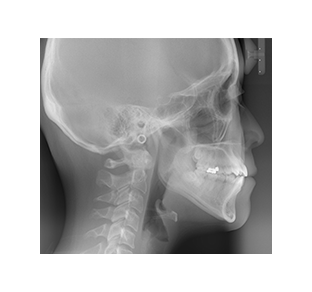

標準(青線)の顎骨と、患者さま(赤線)の顎骨にどのような特徴があるのかを調べます。

標準と比較し分析したデータを数値化します。

緑の項目が標準範囲内で正常、赤の項目は正常値から外れた診断結果として表示されます。

赤字の部分を標準範囲の緑へ変えていくことが、矯正治療の基本的な方針となります。

(※必ずしも、全てをグリーンにするわけではありません)